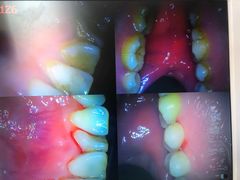

• -新达口腔(华东理工大学店)

zxqvini77 | 21-04-23

报错